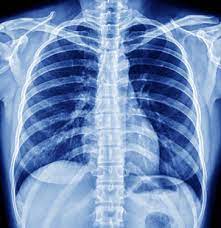

Transforming Healthcare: How Digital X-Rays Revolutionize Patient Experience at Sanya Karond Imaging Center

Enter Sanya Karond Imaging Center, a sanctuary of cutting-edge medical technology. The digital X-ray service offered here is a game-changer for individuals like Rajesh and Priya. Unlike traditional X-rays, digital X-rays at this center provide immediate results, drastically reducing wait times and anxiety. With advanced imaging technology, the center ensures higher precision, aiding in more accurate diagnoses and treatment plans.

But the benefits extend beyond convenience and accuracy. Digital X-rays are environmentally friendly, eliminating the need for chemical processing. They offer enhanced image quality, which aids in early detection of medical conditions, potentially saving lives. For healthcare providers, the efficient storage and easy retrieval of digital images streamline operations, allowing more focus on patient care.